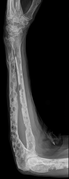

X-ray of the forearm, with lytic lesions.